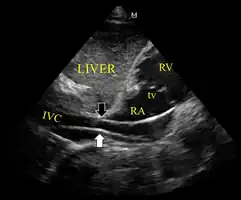

Ultrasound showing the device in the right ventricle -

The device inappropriately passing into the inferior vena cava -